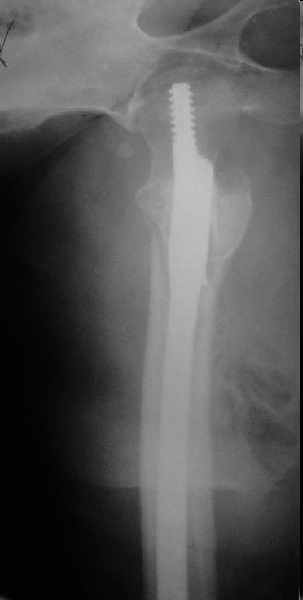

Это типичная проблема, вот аналогичный случай. Удалили, исправили,

фиксировали другим PFN.